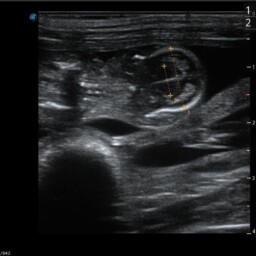

• Monitorowanie przebiegu ciąży (USG bardzo wysokiej jakości, RTG, badania hormonalne)

• Biometria płodowa (wyznaczanie terminu porodu na podstawie pomiarów struktur płodowych)